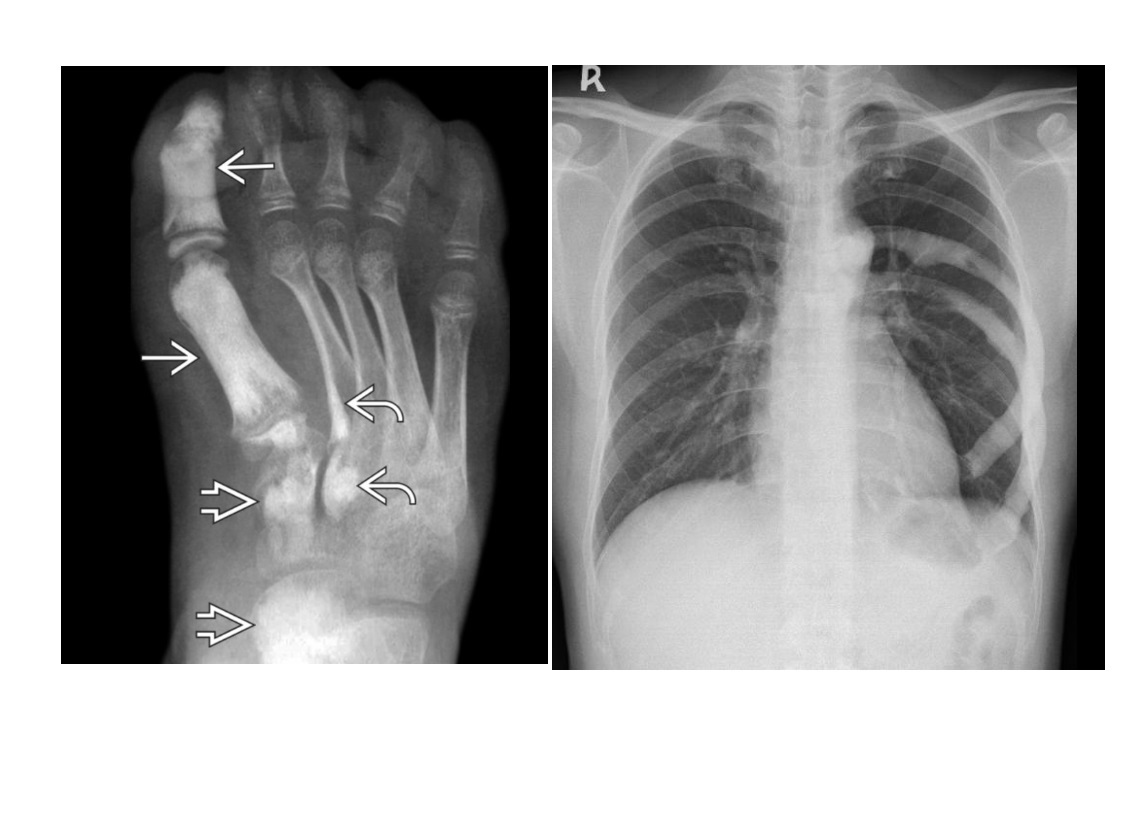

Segond fracture

Lateral tibial plateau

Associated with ACL tear (75%) and internal rotation

MR SL = Medial Reverse Lateral Segond

ENCHONDROMA

Commonest location Hands/feet

Long bones: proximal humerus > distal and proximal femur > proximal tibia

Intramedullary and metaphysis

multiple enchondroma

Maffuci - haemangioma

Olliers - multiple enchondroma only

DDx

-Brown tumor (hyperparathyroidism),

-sarcoid - lace like bone lesion phalanges

-intraosseous ganglion

-metastatic disease.

MRI

T1: low to intermediate signal

Fluid-sensitive sequences: lobulated high signal typical of cartilage lesions

Enhancement: peripheral and septal, accentuating lobules

Chondrosarcoma

May be cecondary to

- Osteochondromas

- enchondromas

Chondrosarcomas occur in the pelvis, femur, humerus.

Skull base, TMJ

-Most well differentiated, low grade = ‘low grade chondroid lesion’ , cant differentate from enchondroma

-Bone infarct

Lobular growth

High 2 signal/STIR, low T1

ring and arcs/chondroid matrix islands on CT

Soft tissue extension

**endosteal scalloping. **

if no mineralized matrix/rings and arcs = aggressive/high grade

How to tell chondrosarcoma from enchondroma ?

* Pathological fracture occurring with minimal trauma

* Multilayered or spiculate periosteal reaction

* Permeative or moth-eaten osteolysis

* Cortical destruction

* A soft tissue mass

Endosteal scalloping more than 2/3 cortex